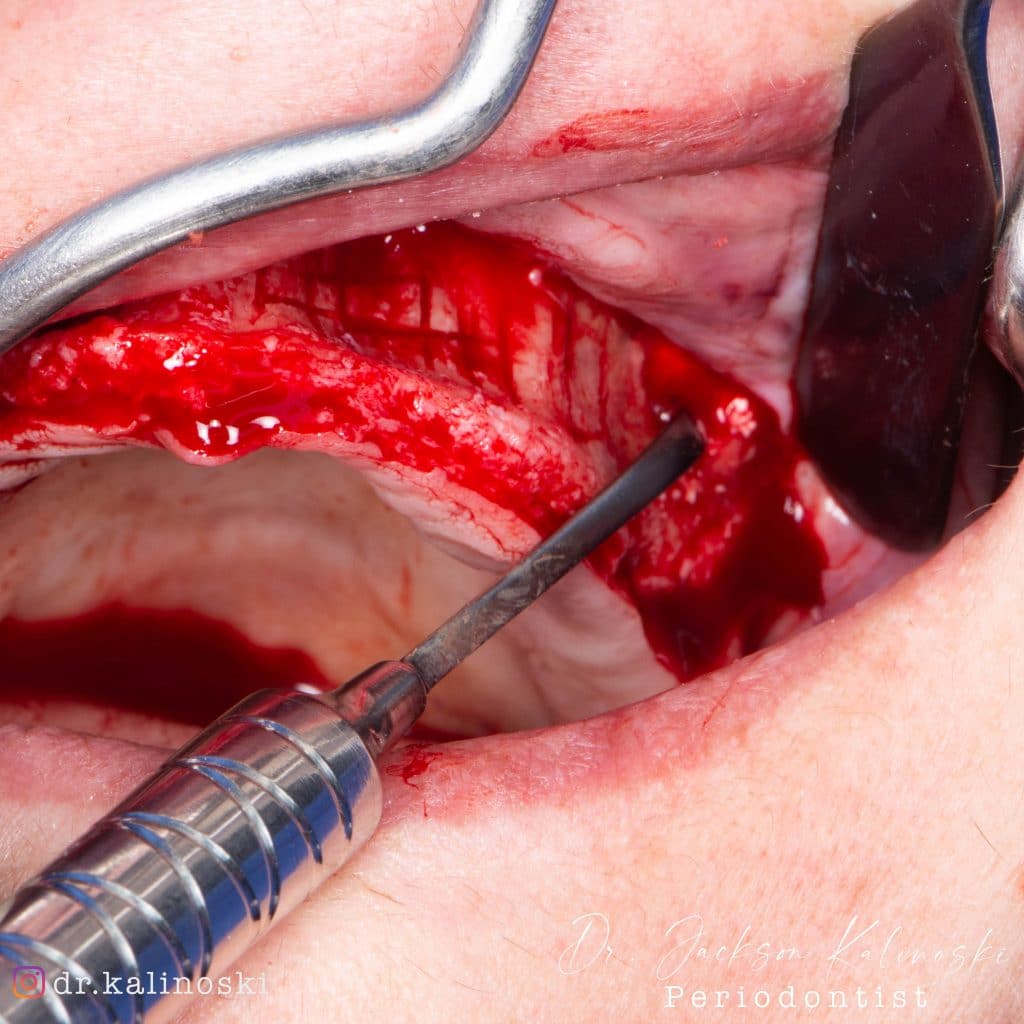

Olá colegas, aqui está um caso didático de reconstrução óssea total da maxila, levantamento do seio maxilar bilateral e bloqueio espesso com aplicação do conceito de PRF e Biotensigrity.

SEM tela, SEM parafusos, SEM membranas de colágeno. Substitua apenas osso aloplástico e sangue.